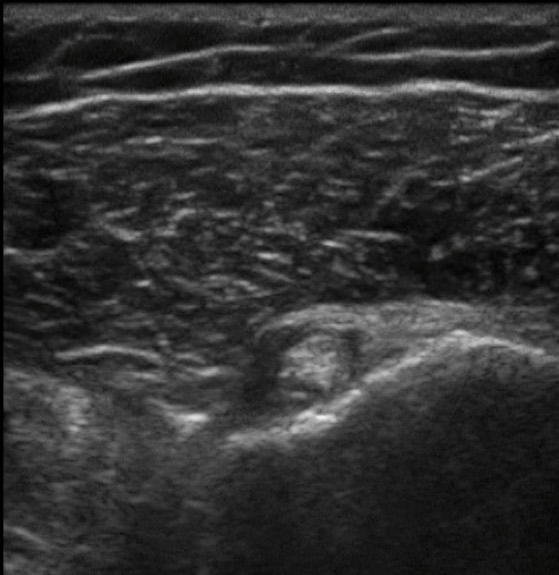

肩上腕二頭筋腱–横断面異常の画像